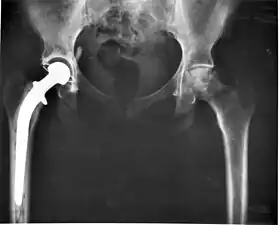

- Class III devices generally require premarket approval (PMA) or premarket notification (510k), a scientific review to ensure the device's safety and effectiveness, in addition to the general controls of Class I. Examples include replacement heart valves, hip and knee joint implants, silicone gel-filled breast implants, implanted cerebellar stimulators, implantable pacemaker pulse generators and endosseous (intra-bone) implants.

Medical implants

An implant is a kind of medical device made to replace and act as a missing biological structure (as compared with a transplant, which indicates transplanted biomedical tissue). The surface of implants that contact the body might be made of a biomedical material such as titanium, silicone or apatite depending on what is the most functional. In some cases, implants contain electronics, e.g. artificial pacemakers and cochlear implants. Some implants are bioactive, such as subcutaneous drug delivery devices in the form of implantable pills or drug-eluting stents.